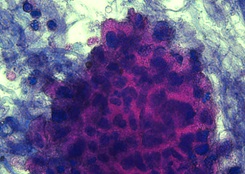

病理検査

手術や生検で採取した臓器や組織を染色、鏡検することで疾病の確定診断などを行います。

- 組織診断

- 細胞診断

- 病理解剖 など

【胃癌の組織診画像】